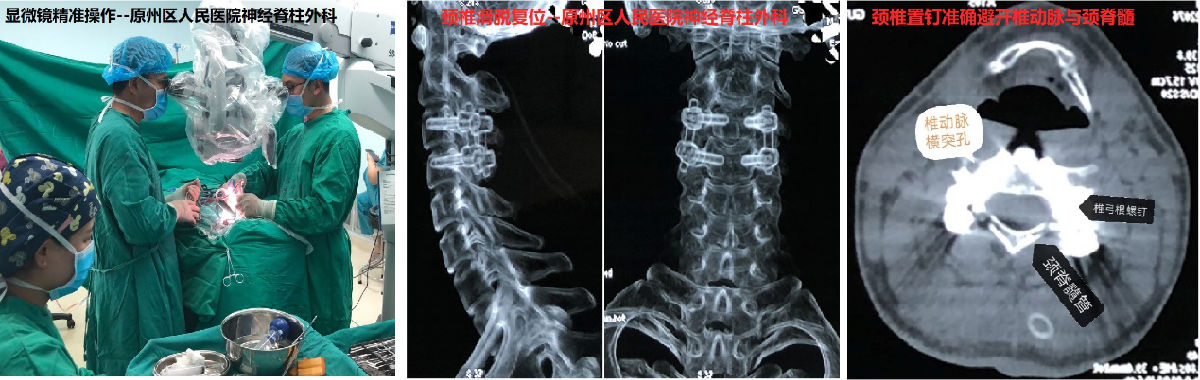

郑小斌介绍,颈椎椎弓根直径较小,外缘毗邻椎动脉,内缘即颈脊髓手术中对椎弓根置钉的准确性要求非常高,否则容易造成瘫痪或脑干、小脑梗死以及大出血等风险,甚至在手术台上即出现呼吸、心跳骤停的可能。于是他们采用了“显微镜技术”。此项技术可以在不过多破坏颈椎正常骨质的前提下,松解绞锁的关节,可视化下探查并准确制备每个置钉通道,确保置钉精确性,通过椎弓根钉复位技术,缩短了颈椎的固定节段,也避免了联合前路手术的需要。

经过3个多小时的手术,王先生推出手术室,神经脊柱外科的手术团队“长长”舒了口气。经过一周多的恢复,患者歪斜的“脖子”已经能摆正回来了,手臂与肩部的麻痛也缓解,顺利的步行出院。